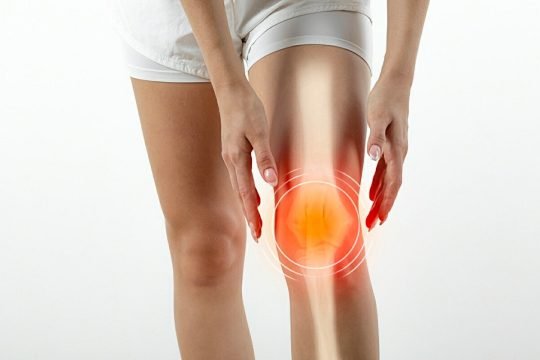

Osteoarthritis (OA) is the most common type of arthritis and a leading cause of pain and disability among older adults. It is marked by the gradual loss of articular cartilage, thickening of the underlying bone (subchondral sclerosis), formation of bone spurs (osteophytes) around joint edges, and changes in joint shape, often resulting in joint enlargement and reduced mobility.